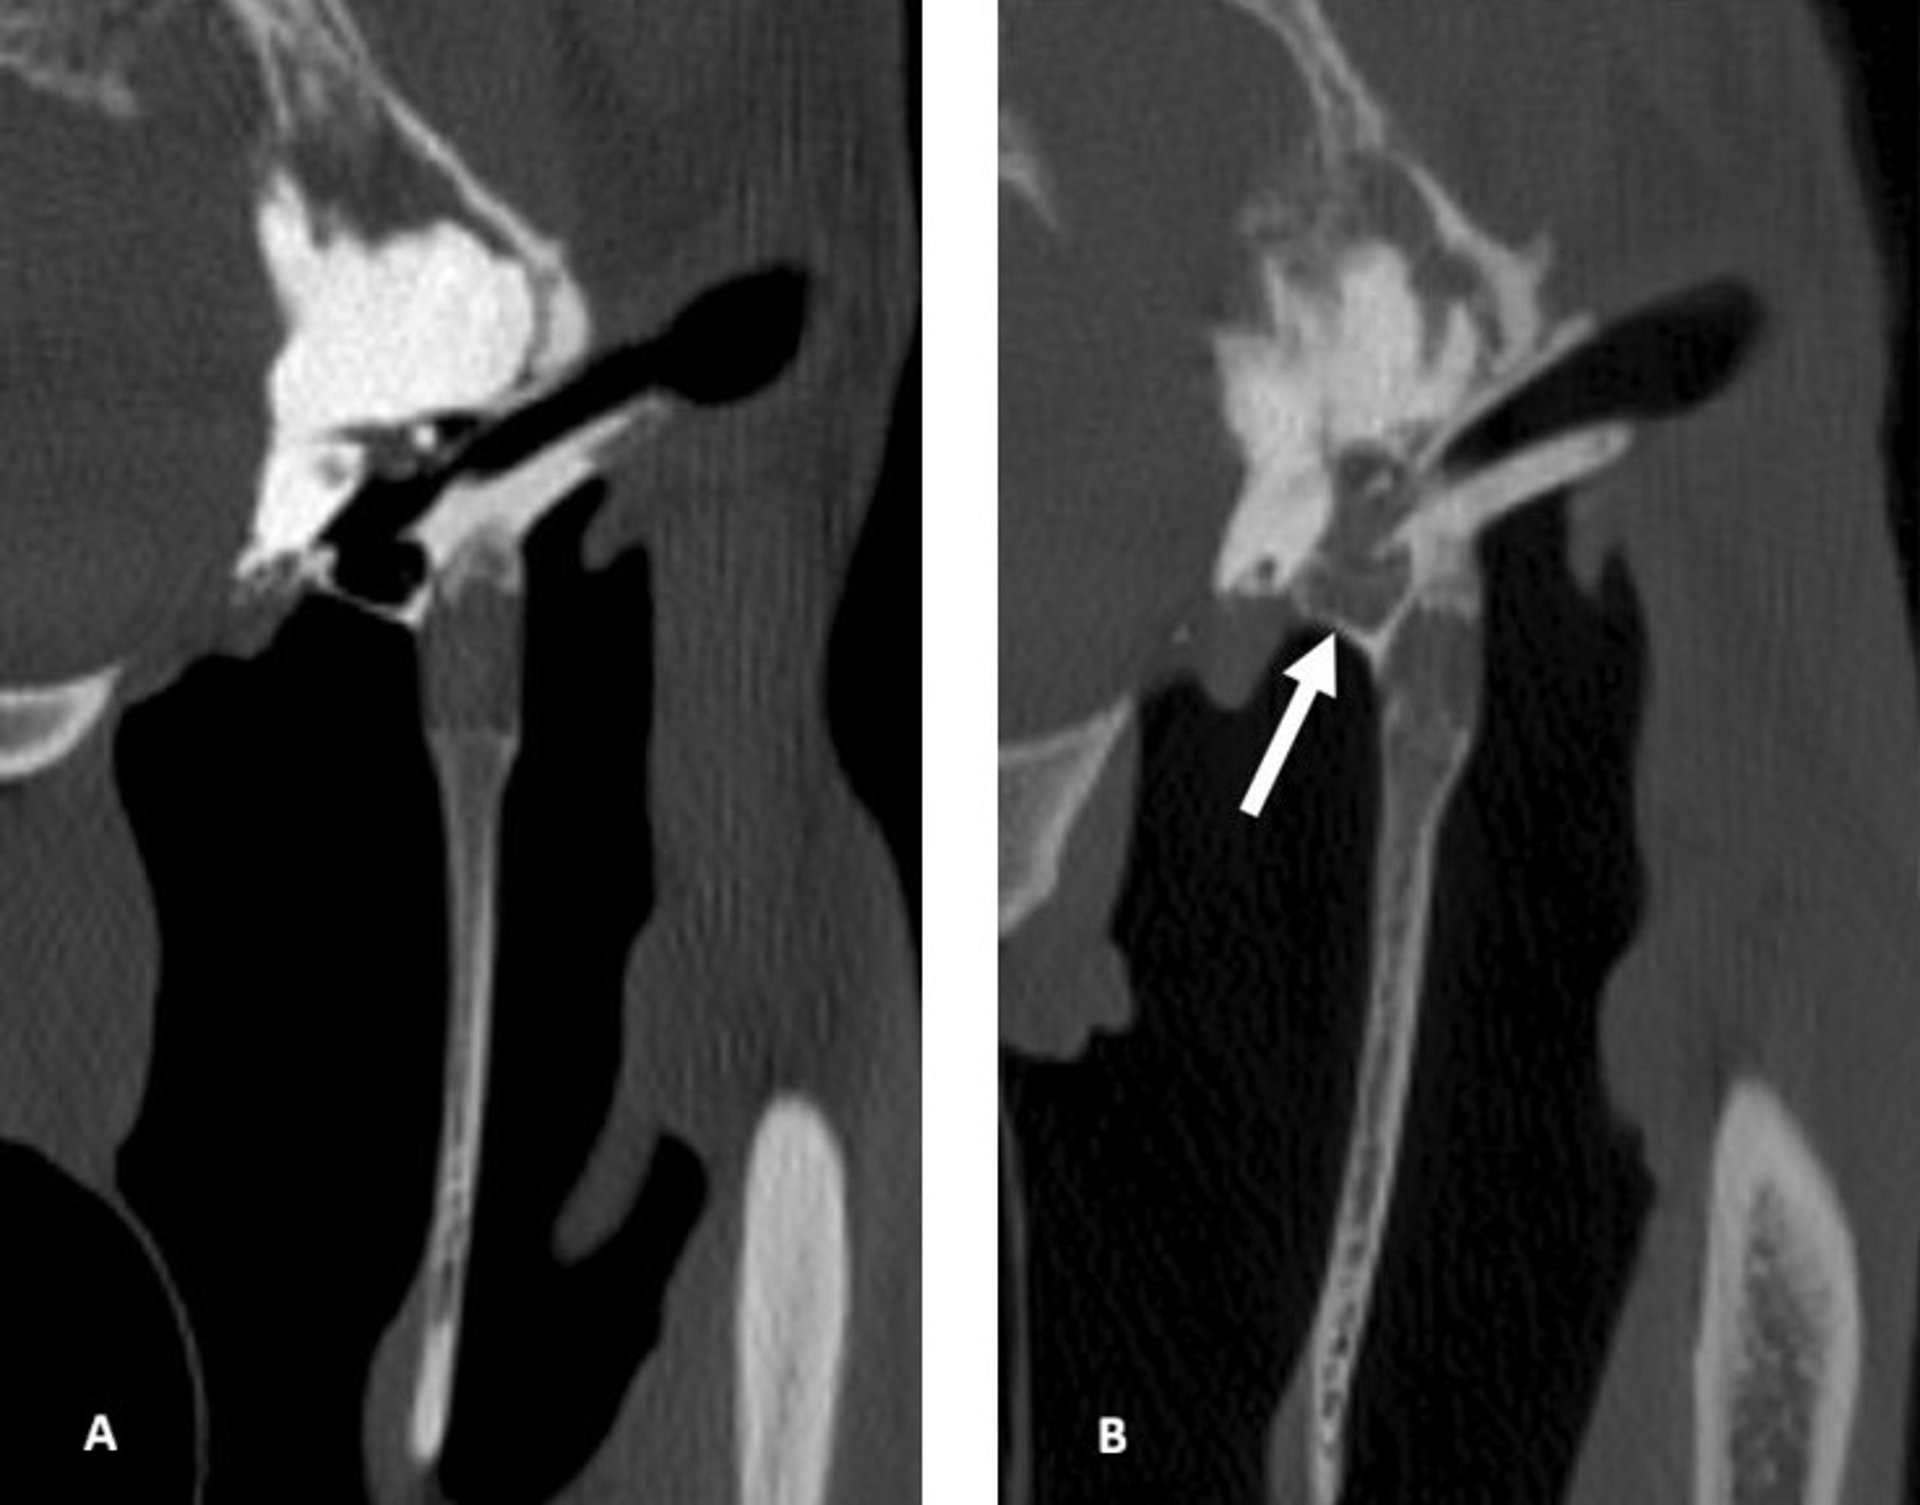

Transverse CT scans of the temporohyoid joint, tympanic bulla, horizontal ear canal, stylohyoid bone, and guttural pouch of a normal horse (A) and a horse with otitis media (B). A. Horse without otitis media: The horizontal ear canal, tympanic bulla, and guttural pouch are air-filled, and the stylohyoid bone and temporohyoid joint are of normal contour. B. Horse with otitis media: The tympanic bulla is filled with fluid (arrow). Helical acquisition, 120 kV and 400 mA, 512 × 512 matrix, 0.625 mm slice thickness, 0.3 mm slice interval, WW: 2800, WL: 800, bone kernel reconstruction.

Images from Dash RF, Perkins JD, Chang Y-M, Morgan RE. Computed tomography of the equine temporohyoid joint: association between imaging changes and potential risk factors. Equine Vet J. 2025. doi:10.1111/evj.14495. © 2025 The Author(s). Equine Veterinary Journal published by John Wiley & Sons Ltd on behalf of EVJ Ltd. Used under CC BY 4.0. Images extracted from Figure 1 (part A) and Figure 3 (part A).